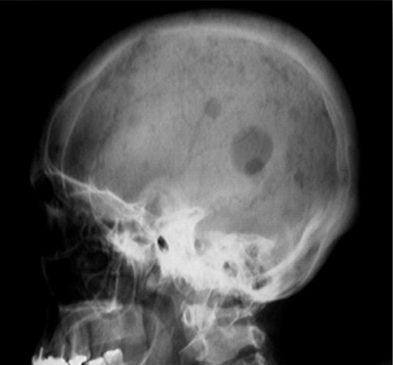

3) X-ray shows punched-out lesions (Figure 2).

Figure 2- Radiograph of skull showing punched-out lesions